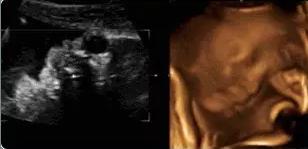

麻麻,我在咬手指哟!

本宝宝有些乏了——揉眼睛

【在妇产科医院,你可以看到这样的胎宝】